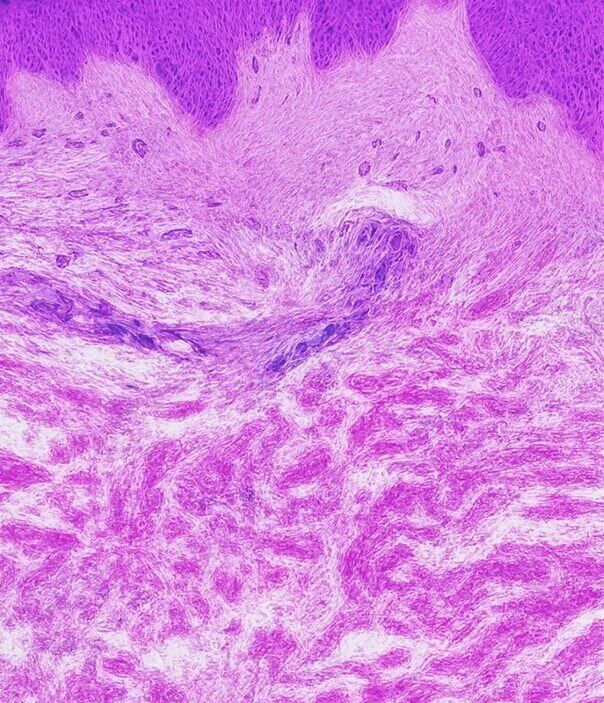

Normal Skin

Smooth and elastic with intact collagen and elastin fibers maintaining firmness and structure.

Striae Rubrae

Smooth and elastic with intact collagen and elastin fibers maintaining firmness and structure.

Striae Albae

Mature white stretch marks where collagen remodeling leads to thinning and loss of pigmentation.

This aging process is accompanied by structural and functional changes in extracellular matrix components such as collagen and elastin. The result in the appearance of fine lines and wrinkles.